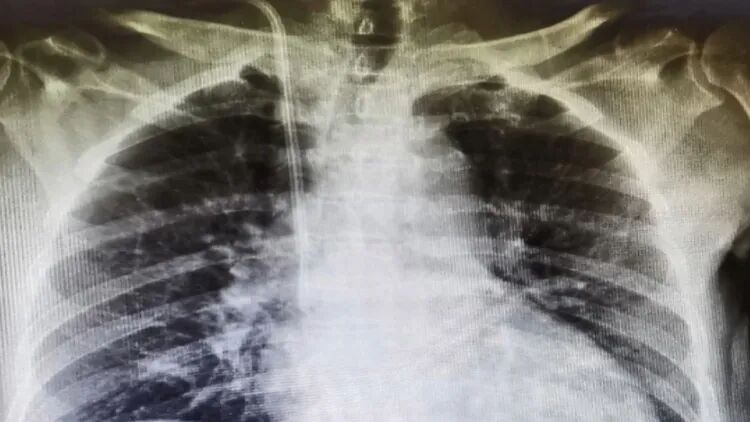

顾先生信以为真,每天在正常服用自身药物的基础上又加量服用保健品,连续服用一个月后,竟出现四肢抽筋、恶心、乏力,最后身体僵硬的症状。经医院检查,肌酐值已经升到了700多,已经演变成了尿毒症。

(图源网络)

刘华常州一院肾内科副主任医师

入院之后,建议他评估了内瘘的情况,考虑内瘘已经成熟了,建议他尽早接受透析替代治疗。

医生介绍,对于慢性肾炎患者的治疗,最重要的是早期用药、早期治疗。在肌酐和尿素升高前,使用药物将血压控制在稳定症状,定期复查,只要肾功能能够长期稳定,就不会发展为尿毒症。但如果患者想要同时服用其他药物或者保健品,需要咨询专科医生进行调整。